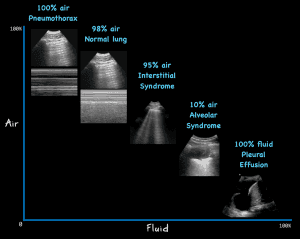

Know the anatomical lung zones and the 10 basic signs of lung ultrasound